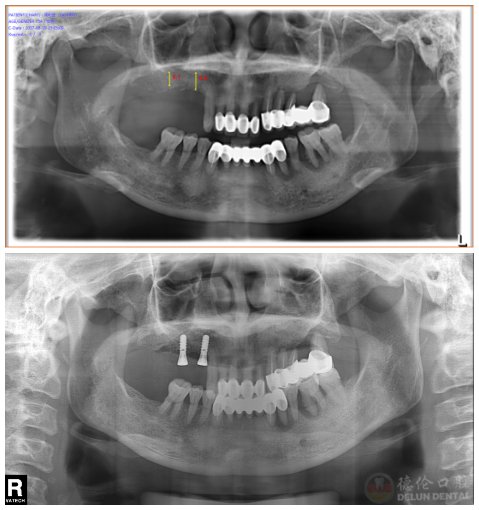

张阿姨手术前后对比照,于左上方种植2颗

今年54岁的张阿姨,右上后牙做烤瓷冠修复十余年,半年前烤瓷冠,随后却出现松动情况,影响进食,摘掉烤瓷冠后希望通过种植牙恢复咀嚼功能。

消毒、麻醉、微创切口、牙根植入……10分钟左右,第一颗新牙就“长”出来了